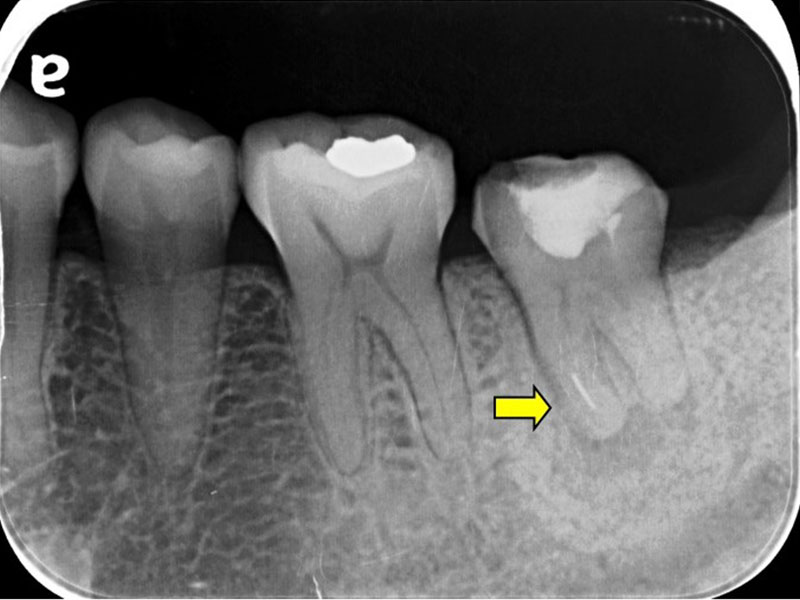

圖例為案例分享:

分離器械移除A-1

分離器械移除A-2